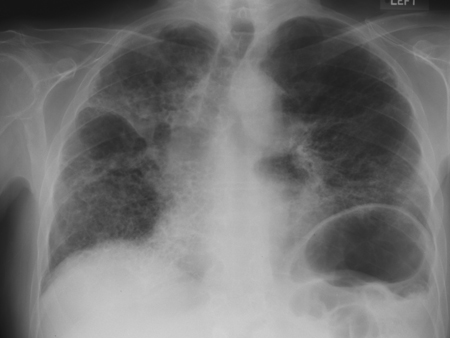

CXR of progressive massive fibrosis due to silica or coal exposure

From the personal collection of Kenneth D. Rosenman, Michigan State University